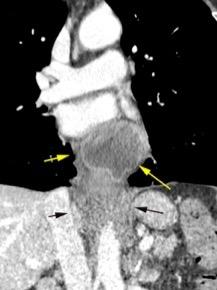

Ganglios retroperitoneales (flechas negras)

germinales del testículo izquierdo Nódulos pulmonares múltiples. (flechas verdes). Ganglios paratraqueales. (flechas amarillas). Dudoso ensanchamiento retrocrural (flechas negras)

Panda A et al. “Straddling Across Boundaries”. Thoracoabdominal Lesions: Spectrum and Pattern Approach. Curr Probl Diagn Radiol, 2015